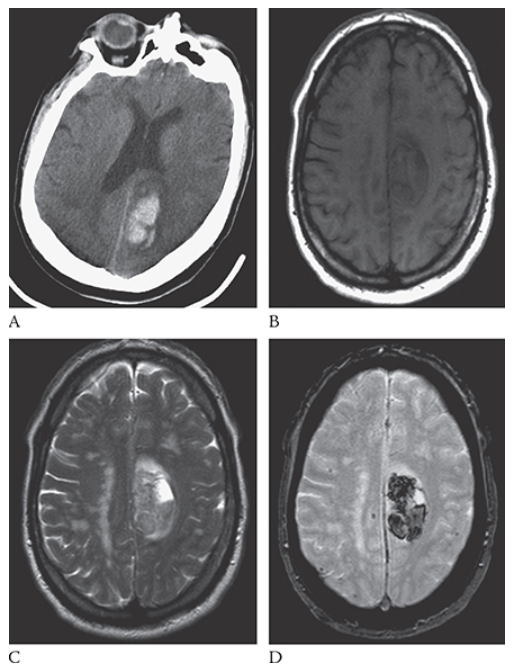

Intracerebral Hemorrhage. Axial NECT image shows an acute hemorrhage in the left posterior parietal lobe. Note the blunting of the left ventricle. An axial T1W image

What is B

Intracerebral Hemorrhage. Axial NECT image shows this area as isointense to hypointense. T2W axial image

What is C

Intracerebral Hemorrhage. Axial NECT image shows the blood to be mildly hyperintense. Gradient echo axial MR

What is D

Intracerebral Hemorrhage. Axial NECT image shows the blood products to be hypointense.